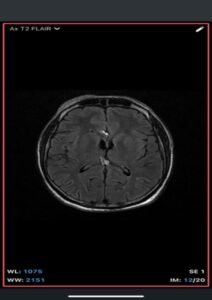

- MRI

- T1-weighted: Hyperintense (fat signal).

- T2-weighted: Variable, usually hyperintense; may show chemical shift artifacts.

- Fat-suppressed sequences: Complete signal suppression confirms fat composition.

- Post-contrast: No enhancement.

- Often associated with:

- Corpus callosum agenesis/dysgenesis

- Interhemispheric cysts